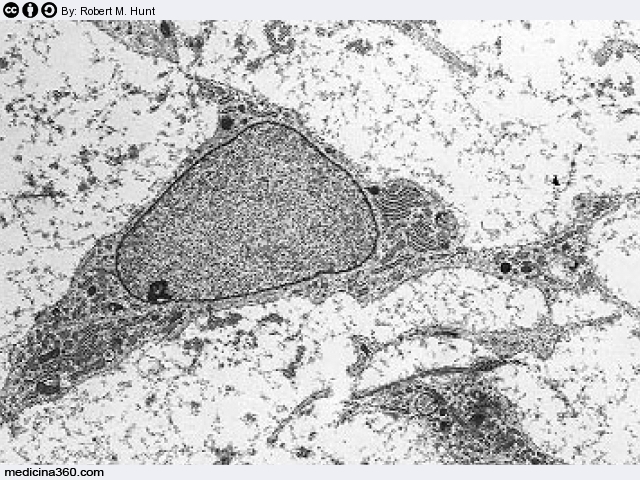

- Si ha clonazione terapeutica se dopo l’impianto del nucleo si stimola semplicemente la riproduzione in vitro della cellula per estrarne (con la distruzione) cellule staminali embrionali utilizzabili per la ricerca e la cura di patologie degenerative (da cui l’aggettivo terapeutico).

Le cellule staminali sono cellule che si possono evolvere vari tipi di cellule e tessuti e sono fondamentalmente di due tipi:

- quelle embrionali che sono in grado di sviluppare in toto un individuo e pertanto sono dette totipotenti,

- quelle adulte che sono presenti nei tessuti di un adulto (sangue, tessuto osseo etc.).

Entrambe i tipi di staminali: embrionali ed adulte, se opportunamente manipolate, possono evolversi in cellule di tessuti diversi. Le embrionali però si accrescono in vitro con maggiore facilità e possono essere più semplicemente orientate.